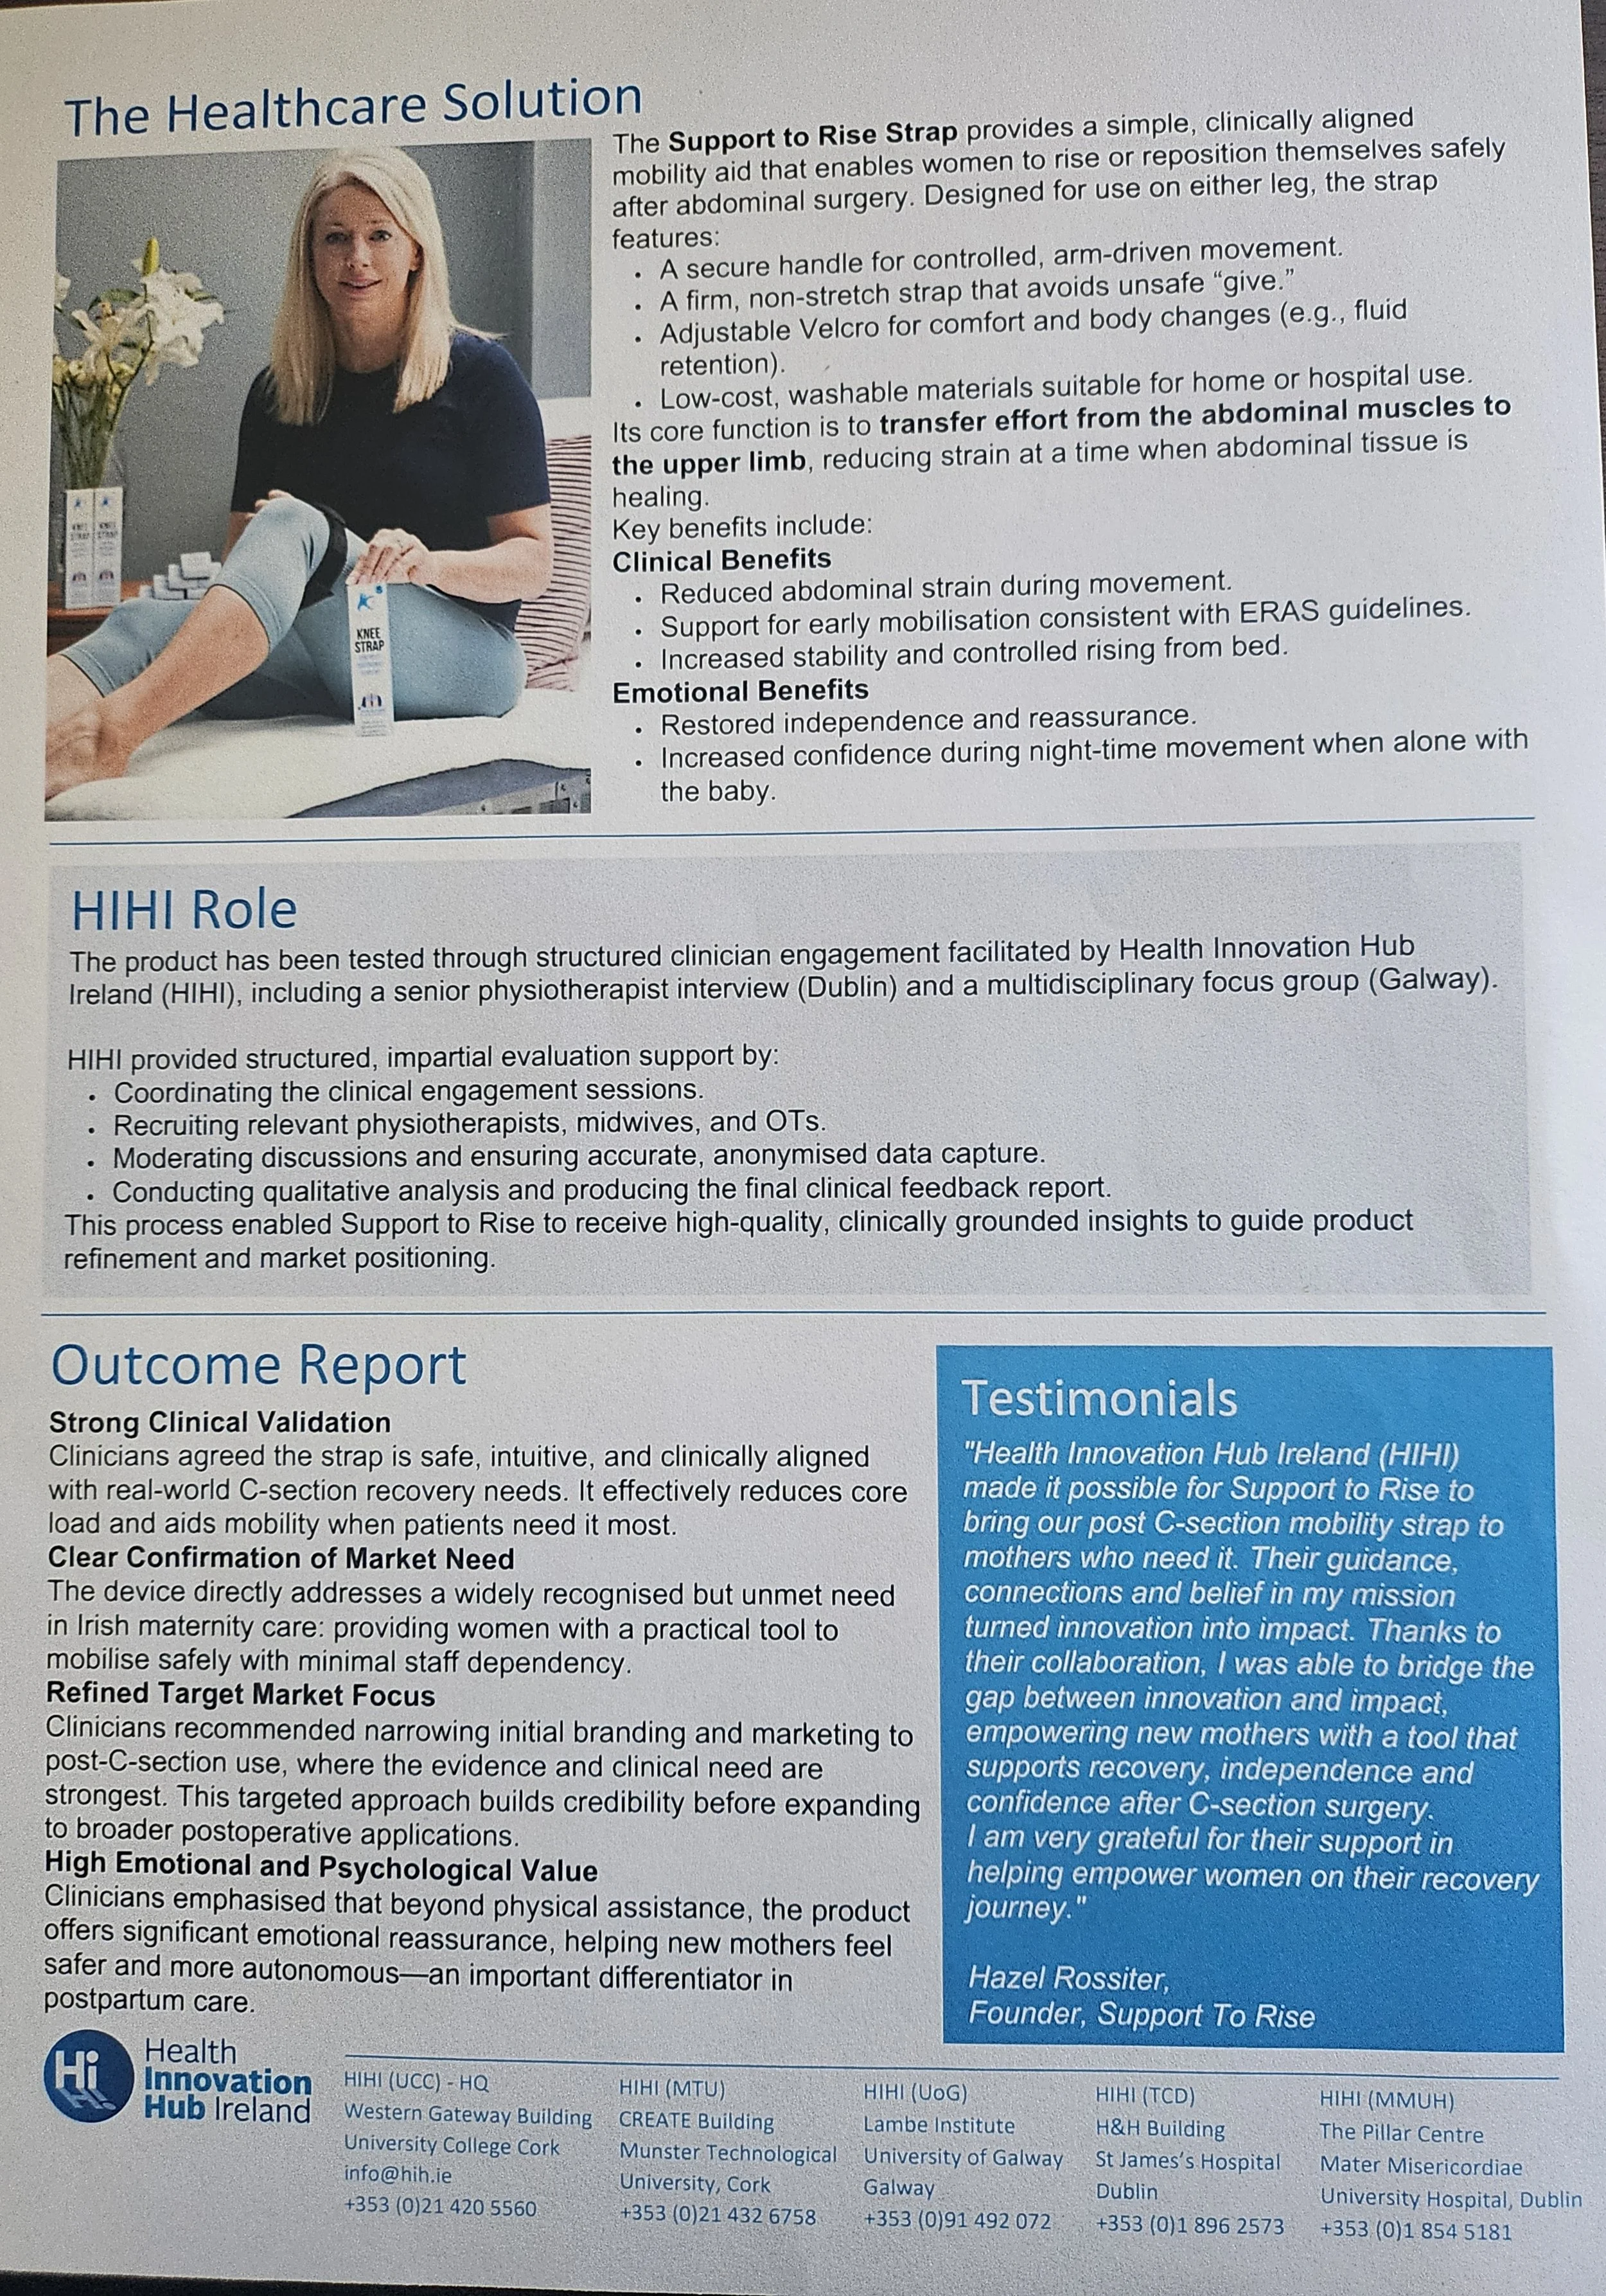

Clinical Evaluation Study - Health Innovation Hub Ireland (HIHI)

Read the Support to Rise Clinical Evaluation Study with the Health Innovation Hub of Ireland (HIHI) gaining the insights from Clinicians, including Midwives, Occupational Therapists and Physiotherapists.

The positive comments from these Clinicians show the support for the strap and its use post C-section to support the Early recovery after Caesarean (ERAC)

You can read the Clinical Evaluation Study report here